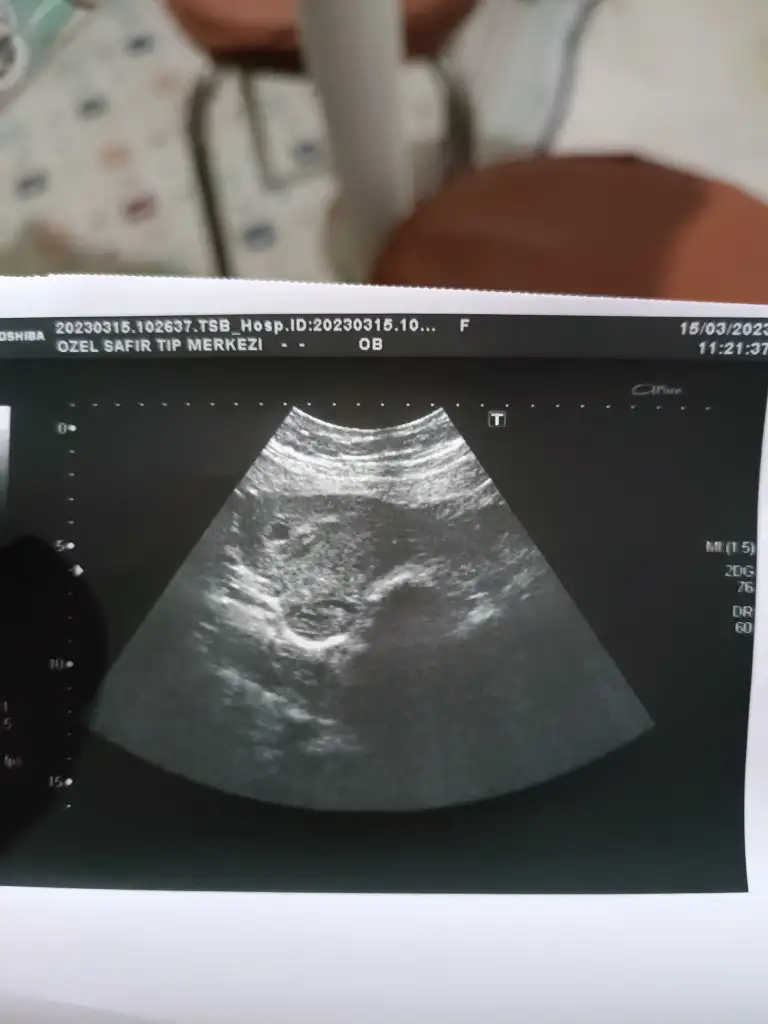

Kızlar doktora gittim kesenin 13,7 mm olduğunu söyledi. Yolk göremedi daha sizin kaç mm de görünmüştü ? Yazarsanız sevinirim . Transfer tarihine göre 4+4 dedi ama keseye göre 5+2 dedi siz hangisini takip ediyorsunuz ?